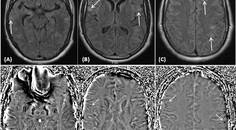

CADASIL Misdiagnosed as Multiple Sclerosis

Anthony Wong, BS; Jacquelyn Johnson, MS, CGCAnthony Wong, BS; Jacquelyn Johnson, MS, CGC